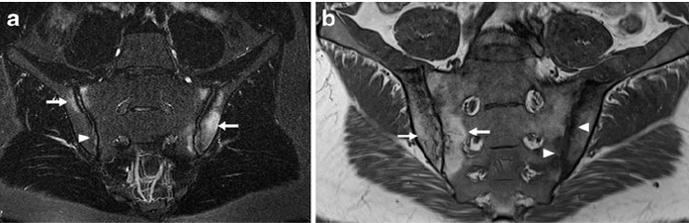

O diagnóstico da Sacroileíte geralmente envolve uma avaliação clínica completa, incluindo a análise dos sintomas e histórico médico do paciente, bem como exames de imagem, como radiografias, ressonância magnética e tomografia computadorizada. Em alguns casos, pode ser necessário realizar exames de sangue e cultura de fluidos corporais para determinar a causa subjacente da inflamação.